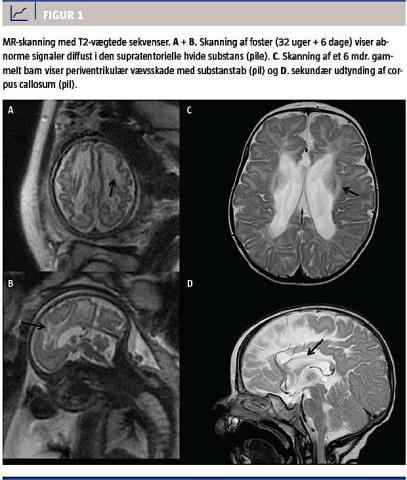

i graviditetsuge 30 + 2 fandtes mistanke om væksthæmning og øget mængde væske cerebralt i de laterale ventrikler. Herefter fulgte et langt forløb med indlæggelser af den gravide kvinde pga. subileus og opkastninger. En MR-skanning i uge 32 + 6 viste diffuse forandringer i den hvide substans periventrikulært i fostrets hjerne (Figur 1). Fødslen blev igangsat i uge 36 + 6 pga. det samlede forløb og mistanken om intrauterin væksthæmning. Fødselsforløbet var ukompliceret, og barnet fik apgarscore 10 efter et minut og efter fem minutter og havde en fødselsvægt på 2.060 g.

Seks måneder gammel blev barnet indlagt pga. tics, skrigeture, manglende hovedkontrol og mistanke om mikrocefali. Man fandt, at barnet havde nedsat bevægelighed i overekstremiteterne, og det greb ikke spontant ud efter ting. En øjenlæge konstaterede, at barnet havde 10% syn på begge øjne. Et EEG viste normale forhold. En MR-skanning af barnets hoved viste et stort ventrikelsystem, glioseforandringer periventrikulært og en meget tynd corpus callosum.

Forandringerne i barnets hjerne var forenelige med asfyktisk skade i fostertilstanden, hvilket kunne forklare barnets symptomer. Barnet havde, da det var 20 måneder gammelt, spastisk tetraplegi.